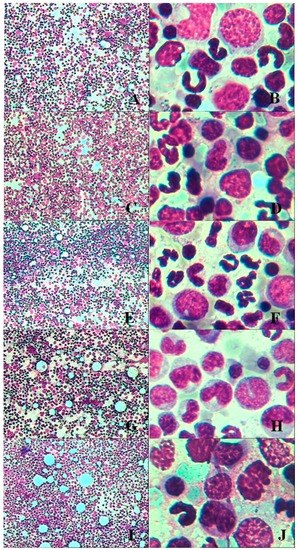

3.2.5. Bone Marrow Examination

Histopathological Findings

| Organ | Findings | Dose (mg/kg/day) | ||||

|---|---|---|---|---|---|---|

| 0 | 5 | 20 | 40 | 80 | ||

| Lung | large confluent bronchopneumonia | 0/4 | 0/4 | 0/4 | 2/4 | 2/4 |

| Bone marrow of sternum | decrease in hematopoietic cell numbers | 0/4 | 0/4 | 0/4 | 2/4 | 3/4 |